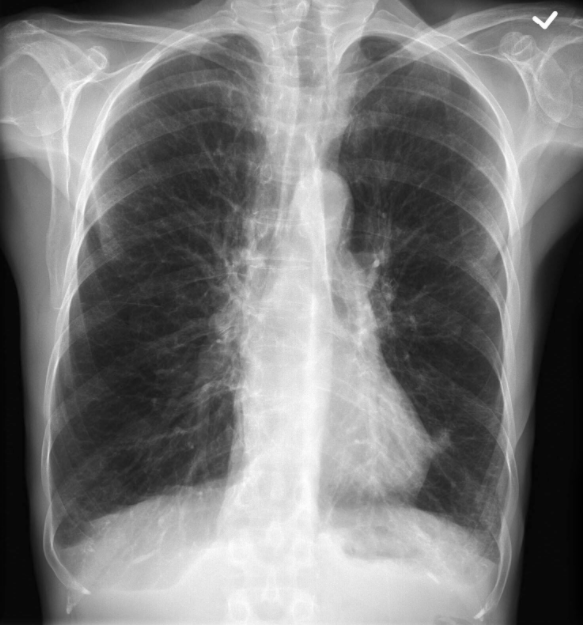

What does this scan show?

CXR demonstrating COPD with hyperinflation

Imaging

Chest x-ray (CXR):

Hyperexpanded

Flattened hemidiaphragms

Hypodense

Saber-sheath trachea